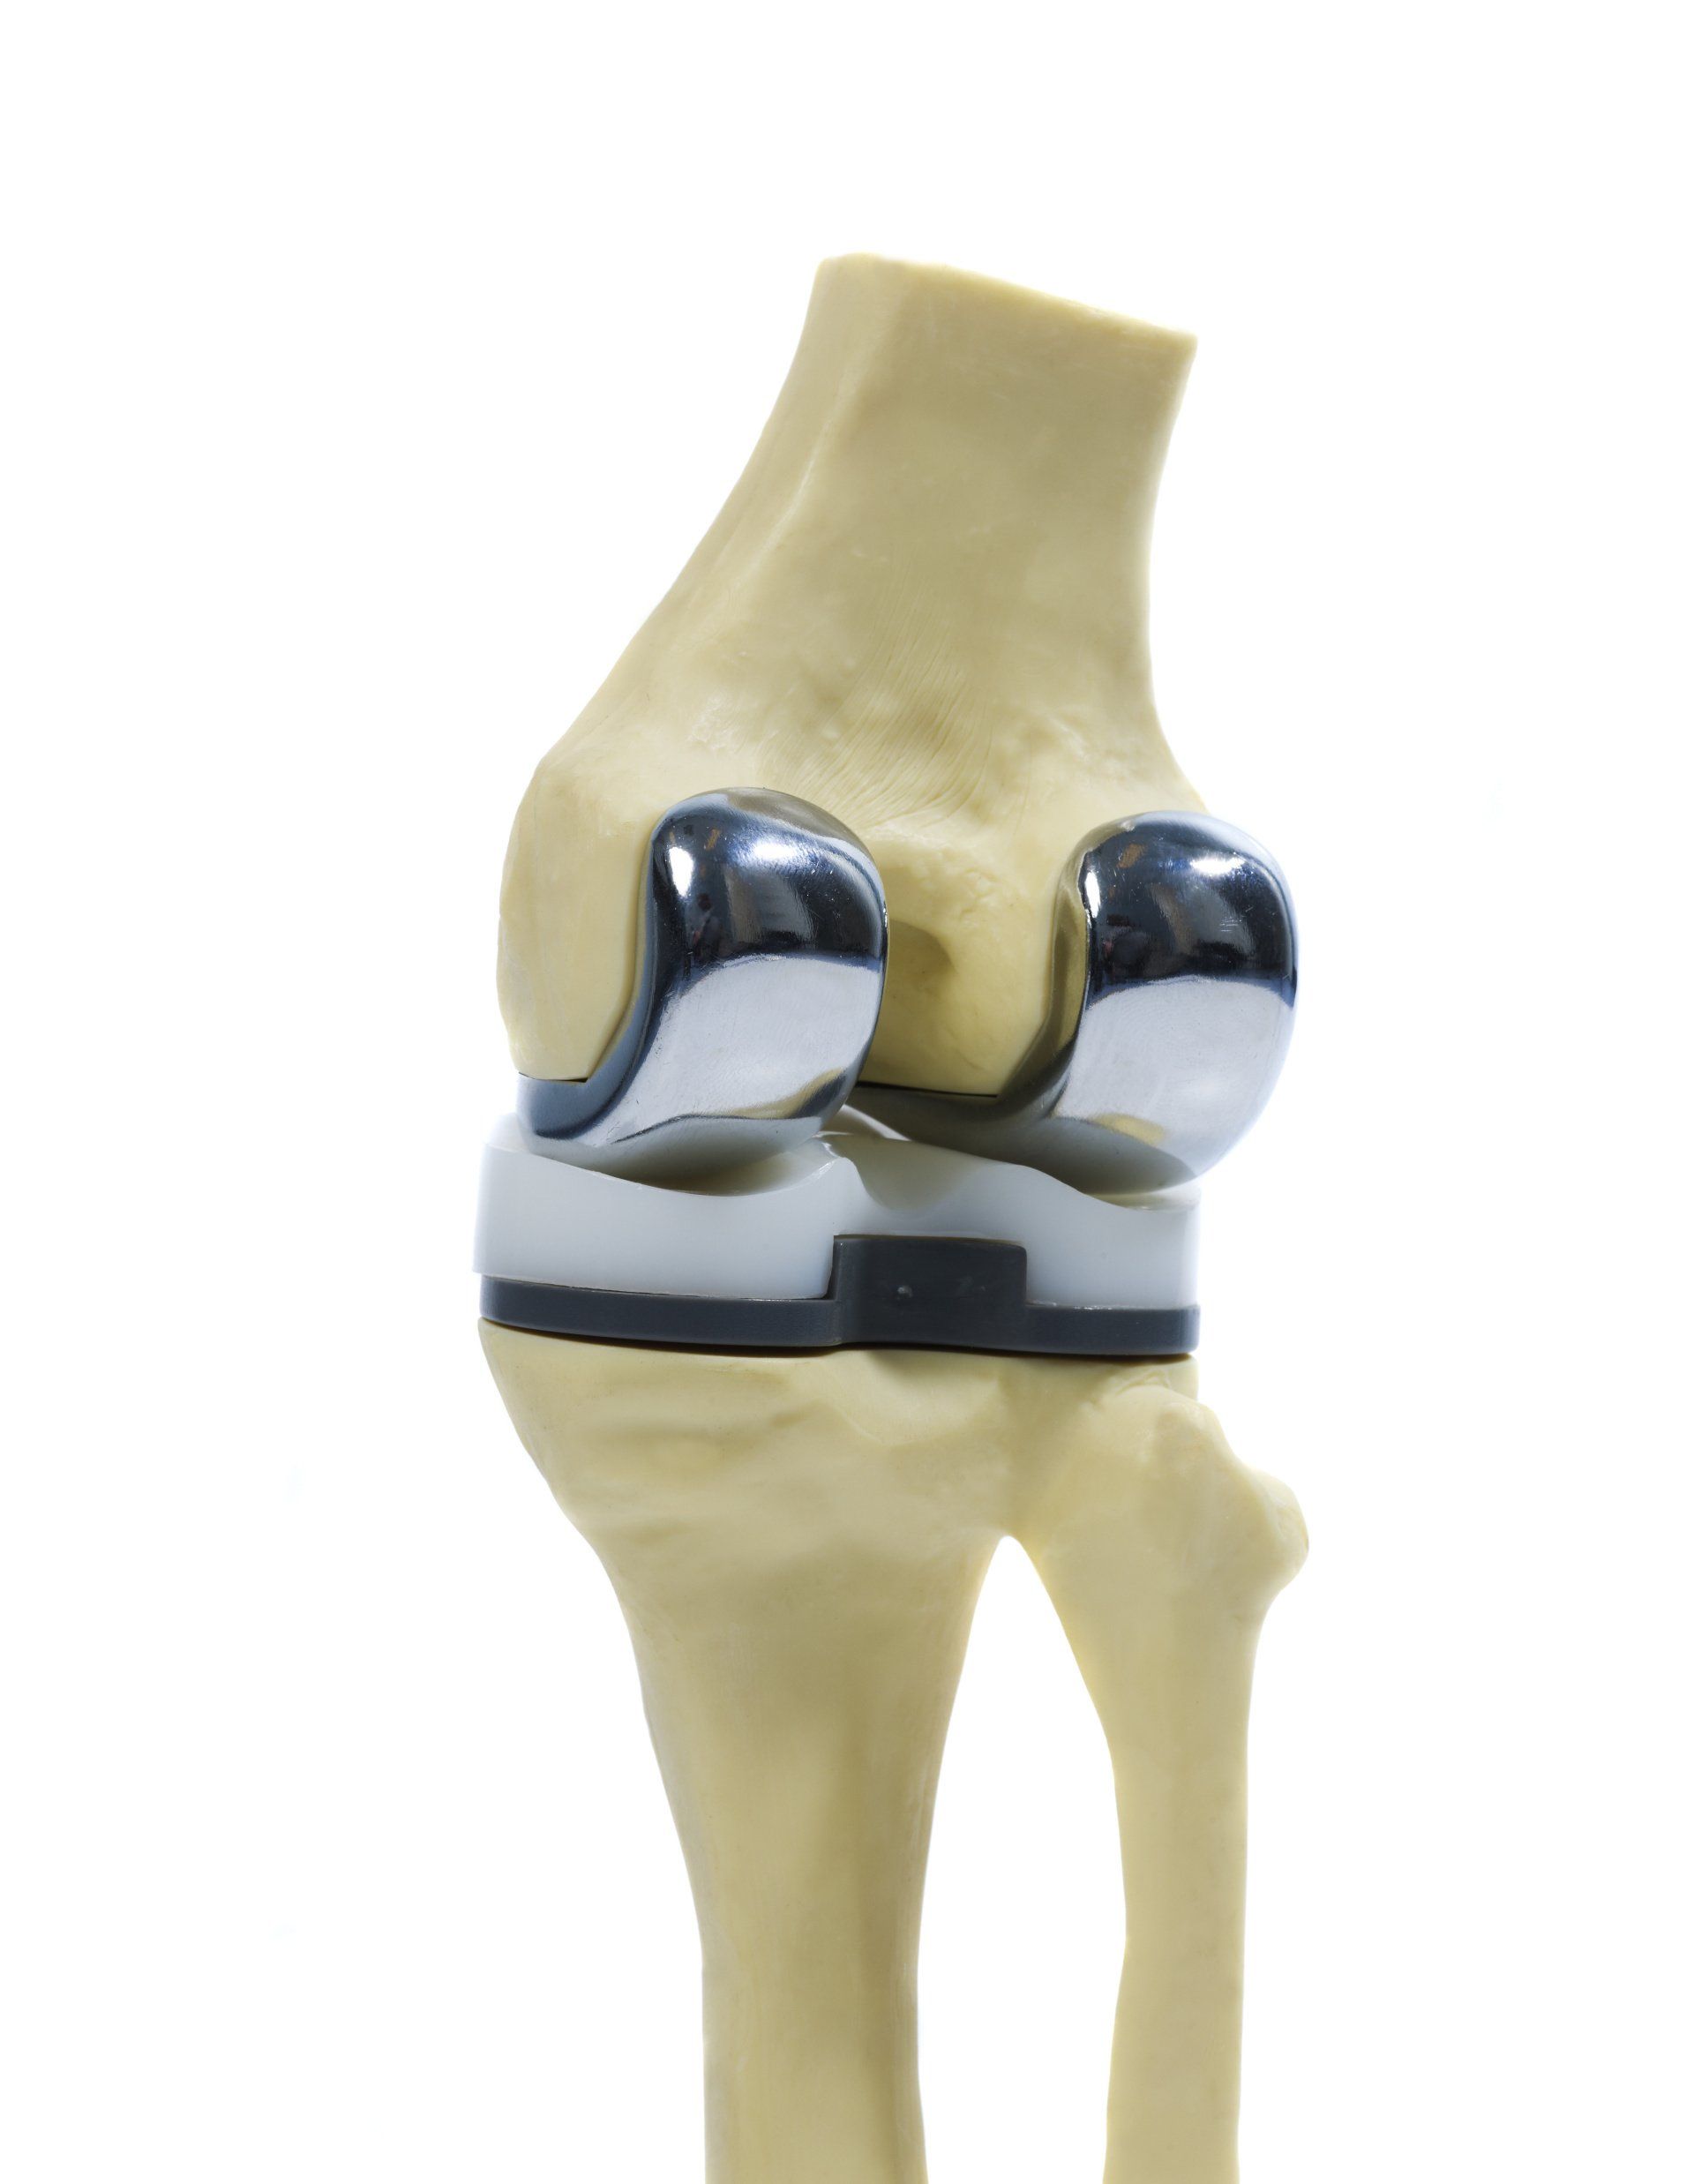

- Η ολική αντικατάσταση του γόνατος (αρθροπλαστική) περιλαμβάνει την αφαίρεση λεπτού στρώματος της αρθριτικής (φθαρμένης) αρθρικής επιφάνειας του μηριαίου και της κνήμης και την αντικατάστασή του με μέταλλο το οποίο καθηλώνεται στη θέση του με ειδικό οστικό τσιμέντο

- Μεταξύ των δύο μεταλλικών επιφανειών τοποθετείται ένα πλαστικό ένθετο (πολυαιθυλένιο) έτσι ώστε να γλιστράνε εύκολα οι μεταλλικές επιφάνειες μεταξύ του μοιραίου οστού και της κνήμης

- Σε επιλεγμένες περιπτώσεις (που εξαρτάται από το βαθμό φθοράς και τον πόνο στο πρόσθιο τμήμα του γόνατος), η οπίσθια επιφάνεια της επιγονατίδας μπορεί επίσης να αντικατασταθεί με πολυαιθυλένιο το οποίο στερεώνεται στη θέση αυτή με τσιμέντο